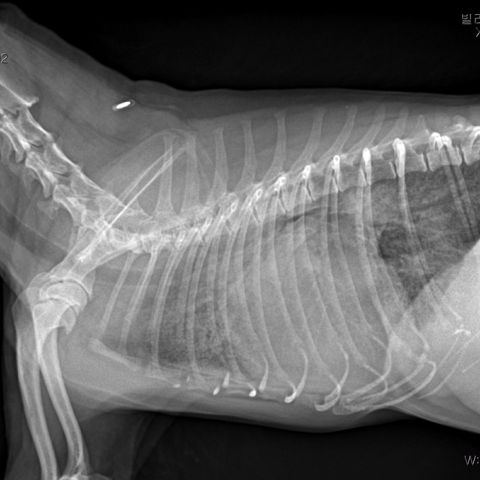

¿ì¸® ¾ÆÀÌÀÇ Ä´Ä´°Å¸²ÀÌ, »êÃ¥À» Èûµé¾îÇÏ´Â Áõ»óÀÌ ´Ü¼øÈ÷ ³ªÀ̰¡ µé¾î¼ À̱⠶§¹®Àϱî¿ä? ½ÉÀ庴Àº ³ë·É°ß 10¸¶¸® Áß 6¸¶¸®¿¡¼ ³ªÅ¸³ª´Â ÈçÇÑ ÁúȯÀÔ´Ï´Ù. ÆÇ¸·ÀÇ º¯¼ºÀ¸·Î ÀÎÇØ ½ÉÀåÀÌ Ä¿Áö¸é ±âħ, ¼ö¸é ½Ã È£Èí¼ö Áõ°¡ µîÀÇ ÀÓ»óÁõ»óÀÌ ³ªÅ¸³¯ ¼ö ÀÖ½À´Ï´Ù. °ü¸®µÇÁö ¸øÇÏ¸é ÆóºÎÁ¾À¸·Î ÀÎÇÑ È£Èí±â ÀÀ±Þ»óȲÀÌ »ý±æ ¼ö ÀÖ½À´Ï´Ù. ÀûÀýÇÑ °Ë»ç¸¦ ÅëÇØ ½ÉÀ庴 ´Ü°èº° °ü¸®¸¦ ¹Þ¾Æ¾ß ÇÕ´Ï´Ù.

½Åü°Ë»ç¸¦ ÅëÇØ ½ÉÀâÀ½ÀÌ Ã»Áø µÇ¸é ,ÈäºÎ ¹æ»ç¼±°Ë»ç, ½ÉÀå ÃÊÀ½ÆÄ, BNP°Ë»ç, Ç÷¾Ð°Ë»ç¸¦ ½Ç½Ã ÇÕ´Ï´Ù. À̸¦ ¹ÙÅÁÀ¸·Î °¢ ´Ü°èº° ½ÉÀ庴 °ü¸®¸¦ ÁøÇàÇÕ´Ï´Ù.

¿ïÇ÷¼º ½ÉºÎÀü

ÆóºÎÁ¾